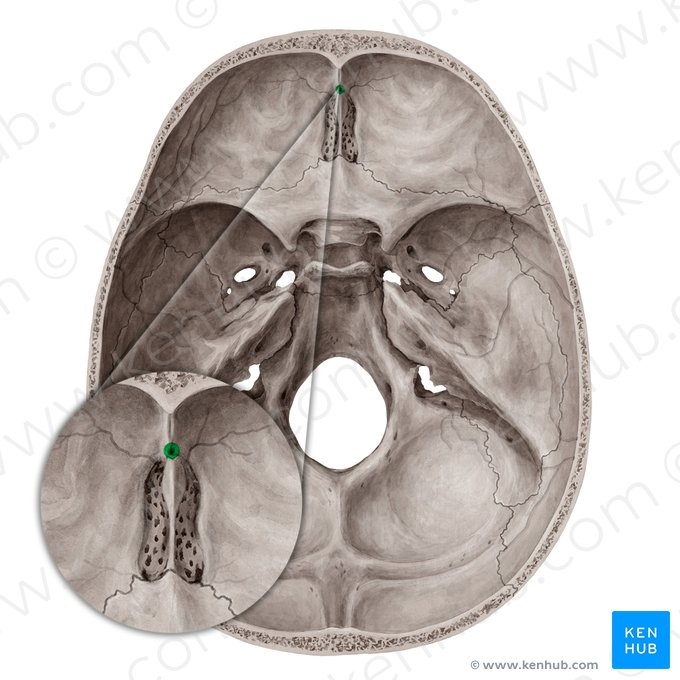

Lámina cribosa del etmoides

Forma parte del piso de la fosa craneal anterior

Perforada por múltiples orificios, por eso el nombre de cribiforme

Dos apófisis alares que articulan con el frontal, creando el foramen cecum

Foramen Caecum

Llamado también Agujero Ciego

Agujeros etmoidales

Anterior y posterior

Apófisis crista galli

Triangular, borde anterior bajo articula con el hueso frontal y completan el agujero ciego(foramen cecum) entre surcos